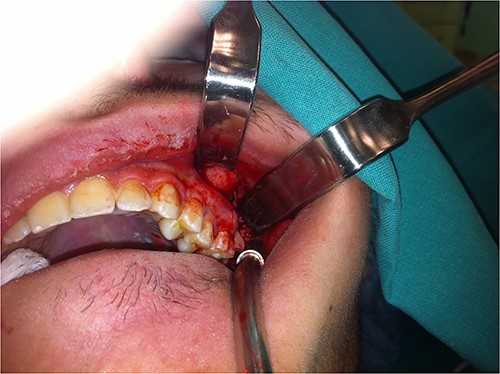

The patient was operated under general anesthesia for better comfort both for the patient and for the surgeon. After local anesthesia with vasoconstriction (lidocaine with adrenaline 1:100 000), an incision was made along the upper buccomaxillary sulcus (Fig. 3). With careful blunt tissue dissection, the crown of the tooth was revealed. With meticulous manipulations to avoid upward displacement of third molar, the tooth was grasped firmly with long Adson forceps and removed (Fig. 4). After copious irrigation of the surgical field, the wound was closed with interrupted resorbable sutures. Pre-operative CT imaging was proved valuable for finding the precise location of the displaced tooth during the operation and avoiding more cumbersome approaches. The surgical procedure lasted about 10 min.

Photograph showing removal of the tooth with the aid of long Langebeck retractors.